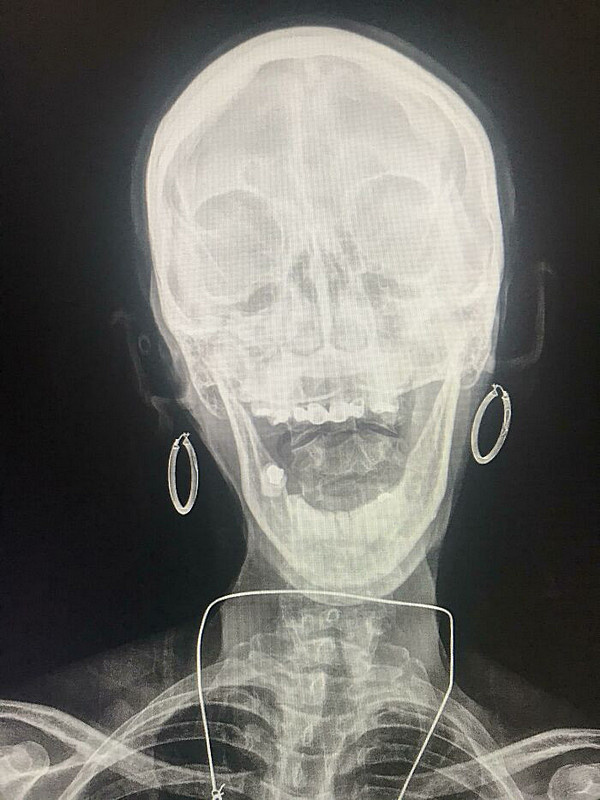

Необычные рентгеновские снимки: то, что скрыто внутри

Раздел: Визуальный дайджест